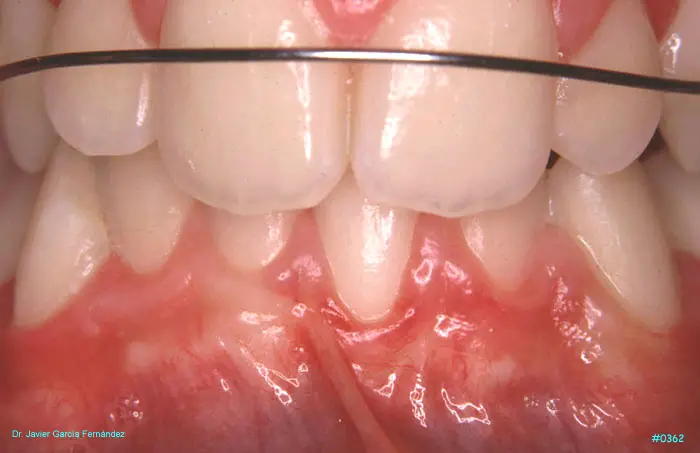

ATLAS DE CIRUGIA PERIODONTAL